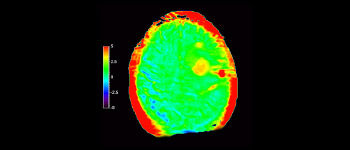

In una società in cui i disturbi neurologici rappresentano un grave problema, Philips si impegna a fornire una efficacia diagnostica senza pari e una guida per il trattamento di tutti i pazienti. Oggi, sebbene la risonanza magnetica sia lo standard di riferimento per l'imaging neuro-oncologico, è comunque possibile migliorarne la precisione nella definizione del grado del tumore e nelle valutazioni di follow-up della terapia. 3D APT (Amide Proton Transfer) è un esclusivo metodo di imaging RM del cervello senza contrasto che permette di ottenere diagnosi più affidabili nel campo della neuro-oncologia. Si avvale della presenza di proteine cellulari endogene per produrre un segnale RM direttamente correlato alla proliferazione delle cellule, un marker dell'attività tumorale. 3D APT è un valido supporto per il personale medico specializzato nella distinzione dei gliomi di grado basso e alto, e nella differenziazione della progressione del tumore rispetto agli effetti della terapia1.

con 3D APT